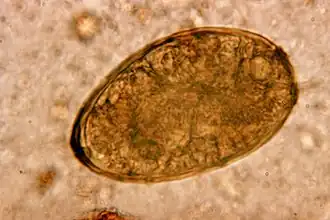

| Eitje van Paragonimus westermani | |||||||||||||||

De ziekte paragonimiasis wordt veroorzaakt door het eten van zoetwaterkreeften en andere kreeftachtigen die niet voldoende zijn doorgekookt. Hierin bevinden zich ingekapselde larven (metacercaria). Deze larven doorlopen een volgend stadium en dringen via het maag-darmstelsel de buikholte in en boren zich door het middenrif en komen zo terecht in de longen waar ze eieren leggen en ze zich inkapselen. De eitjes zijn 0,080 tot 0,120 mm lang en 0,045 tot 0,070 mm breed en bruingeel van kleur. Deze eitjes worden opgehoest en kunnen direct, of via ontlasting in het water terechtkomen. Daar komen de eitjes uit en veranderen in een vrijlevende larve (het miracidium stadium) die zich met trilhaartjes voortbeweegt. Deze larven zoeken een slak op. Er zijn 54 soorten slakken bekend uit de klasse Neotaenioglossa die als tussengastheer kunnen optreden. De larven verlaten de slakken en verplaatsen zich opnieuw in een vrij levend stadium (cercaria-stadium) en nestelen zich in een kreeftachtige.